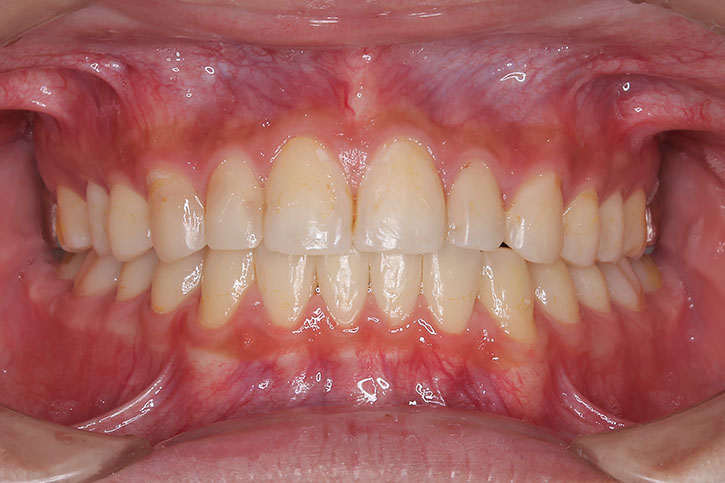

受け口の治療は、前歯の交換時期(小学校1年生ごろ)から小児矯正を始めることをお勧めします。

この時期に前歯の咬み合わせを治しておくことが後々重要になります。